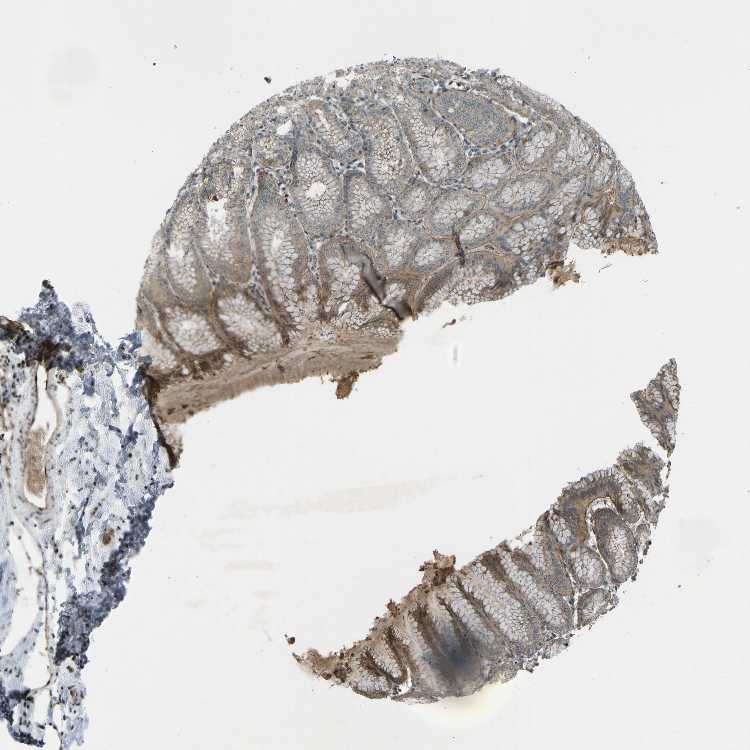

STOMACH 1 - Antibody stainingi

Antibody staining in the annotated cell types in the current human tissue is reported as not detected, low, medium, or high, based on conventional immunohistochemistry profiling in selected tissues. This score is based on the combination of the staining intensity and fraction of stained cells.

Each image is clickable and will lead to virtual microscopy that enables deeper exploration of all samples and also displays staining intensity scores, fraction scores and subcellular localization as well as patient and tissue information for each sample.

Antibody HPA018035

Glandular cells Medium